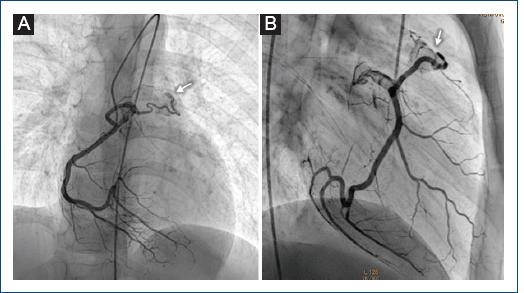

Figura 2 Coronariografía derecha que muestra una fístula coronaria inmediatamente después del origen de la coronaria derecha que llega al tronco pulmonar (flecha). A: proyección posteroanterior. B: proyección oblicua anterior derecha.

Varón de 11 años al que se detectó un soplo cardiaco a la edad de 8 años por médico pediatra, quien comentó al familiar que este era un soplo «inocente» y se le dio vigilancia por 3 años. Al no modificarse el soplo con el tiempo, es enviado a nuestra institución, asintomático cardiovascular. Exploración física: buen crecimiento y desarrollo, soplo expulsivo II/IV, en mesocardio, tono agudo, timbre piante, sin modificación con maniobras, hígado no congestivo, pulsos normales en las cuatro extremidades, resto de la exploración sin alteraciones. Electrocardiograma y telerradiografía de tórax normales. Ecocardiograma transtorácico con presencia de flujo continuo retrógrado por Doppler color de 1 mm que llega al tronco de la arteria pulmonar, sin lograr determinar su origen (Fig. 1 A y B). La angiografía por tomografía computarizada (angio-TC) de tórax reporta una estructura vascular delgada, elongada, que comunica aparentemente la aorta ascendente con el tronco de la arteria pulmonar (Fig. 1 C). Se propone cateterismo cardiaco diagnóstico. En la angiografía de la aorta ascendente y en coronariografías selectivas se aprecia una fístula coronaria que nace inmediatamente después del ostium de la coronaria derecha, de 1 mm de diámetro, con un trayecto anterior e izquierdo sobre el infundíbulo pulmonar, drenando a la parte proximal del tronco pulmonar por arriba del anillo valvular pulmonar (Fig. 2 A y B), y una segunda fístula con origen en el tercio proximal de la arteria coronaria descendente anterior de 1 mm, drenando de igual forma en el tronco de la arteria pulmonar (Fig. 3 A y B), ambas de 0.15 mm a su llegada al tronco pulmonar. Debido al tamaño tan pequeño de las fístulas, se decide no realizar intervencionismo y continuar la vigilancia.